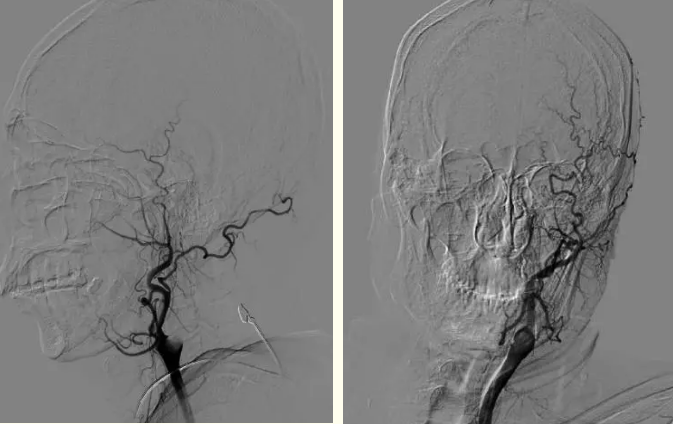

术中画面

全脑血管造影显示:左侧颈内动脉起始段闭塞

全脑血管造影显示患者左侧颈内动脉起始段闭塞,血栓负荷量大,手术难度较大,刘忠锦团队立即行机械取栓,经抽吸导管抽吸出大量血栓栓子,再给予支架取栓治疗,不断地努力后,终于打开了闭塞的大脑中动脉。造影显示右侧颈内动脉、大脑中动脉再通,观察10分钟后血流仍通畅,患者得救了,医护人员松了一口气。

术后血管再通影像